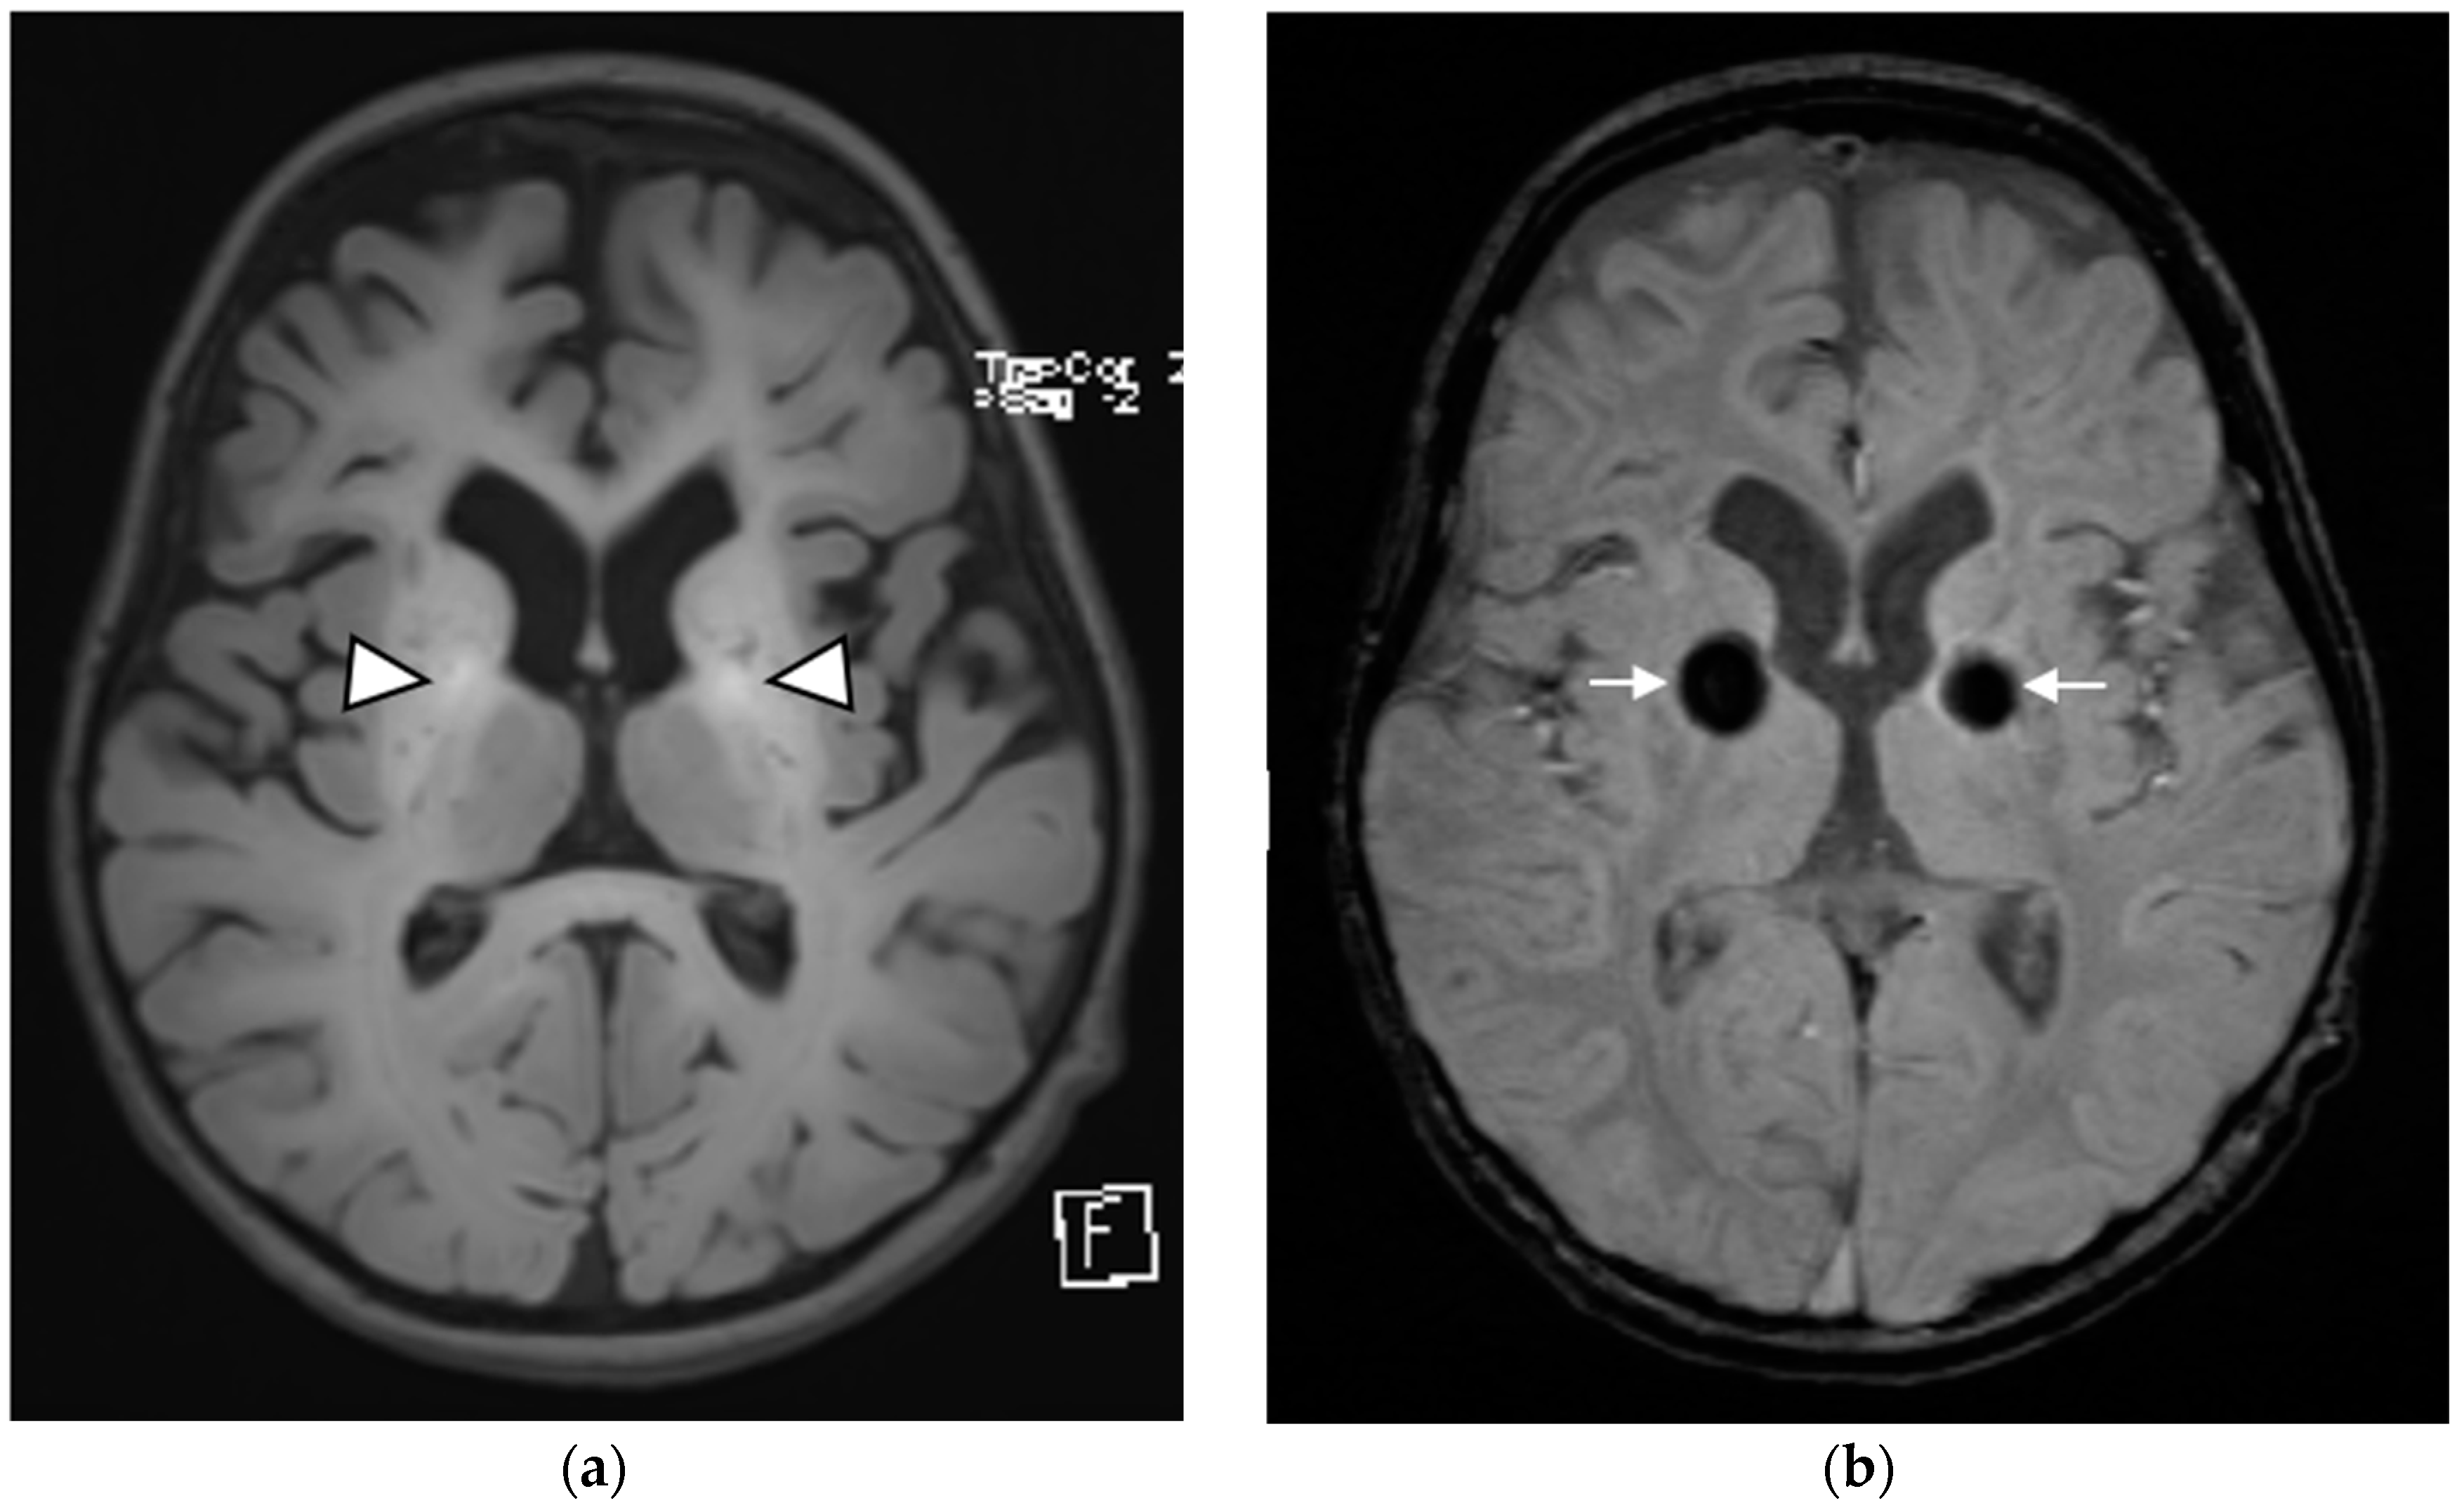

| Brain MRI findings at the time of diagnosis | Symmetrical involvement of the basal ganglia, with decreased T2 and increased T1 signal intensity Mild global atrophy Mildly enlarged eye globes | Symmetrical involvement of the basal ganglia, with decreased T2 and increased T1 signal intensity, and the involvement of cerebellar white matter and posterior brain stem to a lesser degree | Symmetrical involvement of the basal ganglia, tegmentum of the midbrain, posterior tegmentum of the pons, both superior cerebellar peduncles and dentate nuclei, with decreased T2 and increased T1 signal intensity |

| Follow-up brain MRI | Not performed | Similar changes to those observed at initial MRI, with no new lesions and no extension of previous lesions | Similar changes to those observed at initial MRI, with no new lesions and no extension of previous lesions |